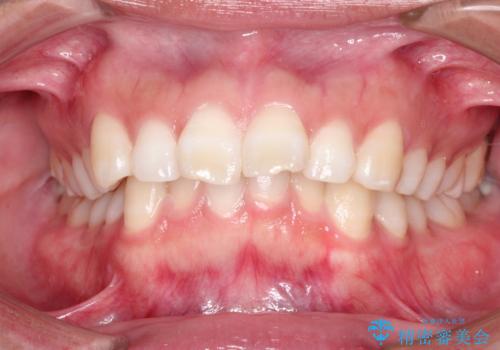

- 出っ歯を主訴に来院されました。

下の歯並びに対して、上の歯が全体的に前方に位置している状態でした。

抜歯をすることでしっかり前歯を後方に移動させて、引っ込めることができました。